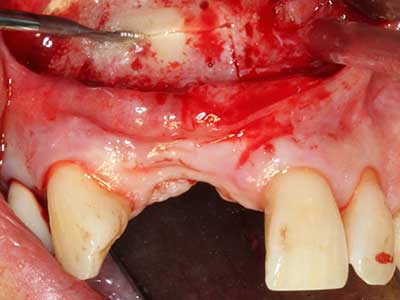

Indikation: Bone Splitting

Knochengewebe ist nicht nur rein mineralisch, sondern auch in wesentlichen Anteilen aus Kollagenfasern aufgebaut. Dies gewährleistet neben einer guten Druckfestigkeit eine gewisse Flexibilität, welche für die Durchführung von Augmentationen genutzt werden kann. Bei der klassischen Expansionsplastik im Sinne eines Bone Splittings wird der atrophierte Kieferkamm in seiner Längsachse gespalten und nach Erreichen einer ausreichenden Osteotomietiefe vorsichtig aufgedehnt (Abb. 13-16), idealerweise ohne den Kiefer wesentlich zu deperiostieren (Brugnami, Caiazzo et al. 2014, Stricker, Fleiner et al. 2014). Bewährt haben sich Schrauben- und Plattensysteme mit zunehmender Expansionsdistanz, um die beiden Knochenlamellen unterhalb der Bruchschwelle voneinander zu distanzieren. In der Regel werden Restknochenbreiten von mindestens 3-4 mm gefordert (Chiapasco, Zaniboni et al. 2006), um eine ausreichende Flexibilität und knöcherne Bedeckung der einzubringenden Implantate zu gewährleisten. Ggf. kann eine ein- oder beidseitige vertikale Entlastungsosteotomie die Flexibilität verbessern. Als Alternative zur klassischen Technik wurde eine Kombination mit weiteren augmentativen Techniken vor allem auf der bukkalen Seite beschrieben.

Mittels Piezosägen erfolgt die Anlage des Splittings besonders schonend und ohne wesentliche Dimensionsverluste, so dass sich keine signifikanten Unterschiede von Implantaten im gesplitteten Kiefer im Vergleich zum nicht defizitären Alveolarkamm gezeigt haben (Chiapasco, Zaniboni et al. 2006, Danza, Guidi et al. 2009). Gerade beim lokal begrenzten und tiefen Splitting ist jedoch stets auf eine ausreichende Wasserkühlung zu achten, um thermische Belastungen in den apikalen Osteotomiebereichen zu vermeiden.